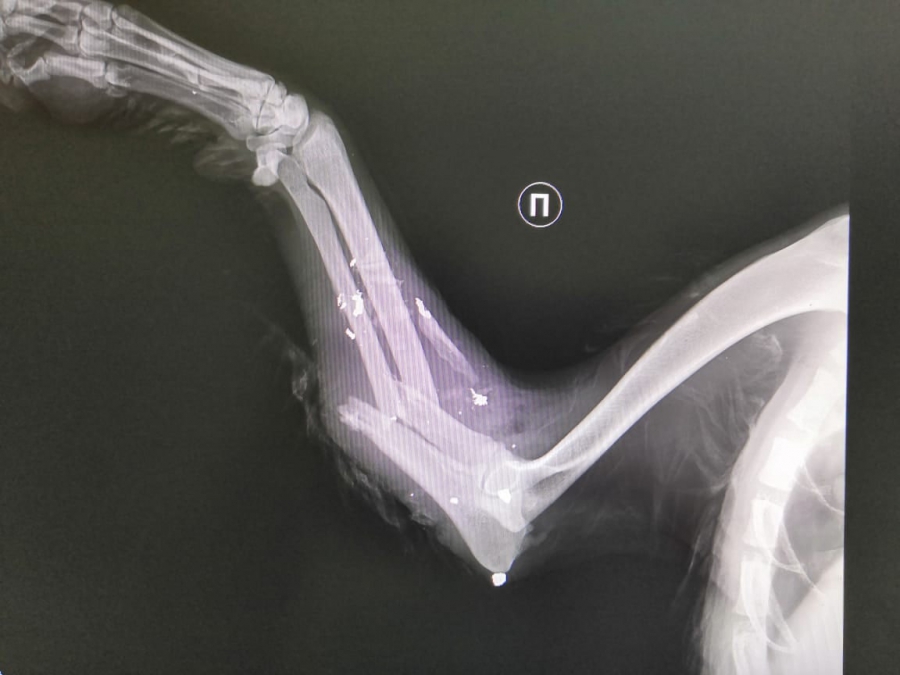

«У него огнестрельное ранение лицевой части, шеи, правой грудной конечности. Оскольчатый, открытый перелом локтевой и лучевой костей справа, с кровотечением!» - рассказали волонтеры.

При обследовании выяснилось, что травмы уже не свежие, они загноились.

За короткое время организация собрала некоторую сумму в качестве помощи. Проведена операция по восстановлению костей, удалили осколки и раздробленные зубы, установлен дренаж. Возможна еще одна операция.